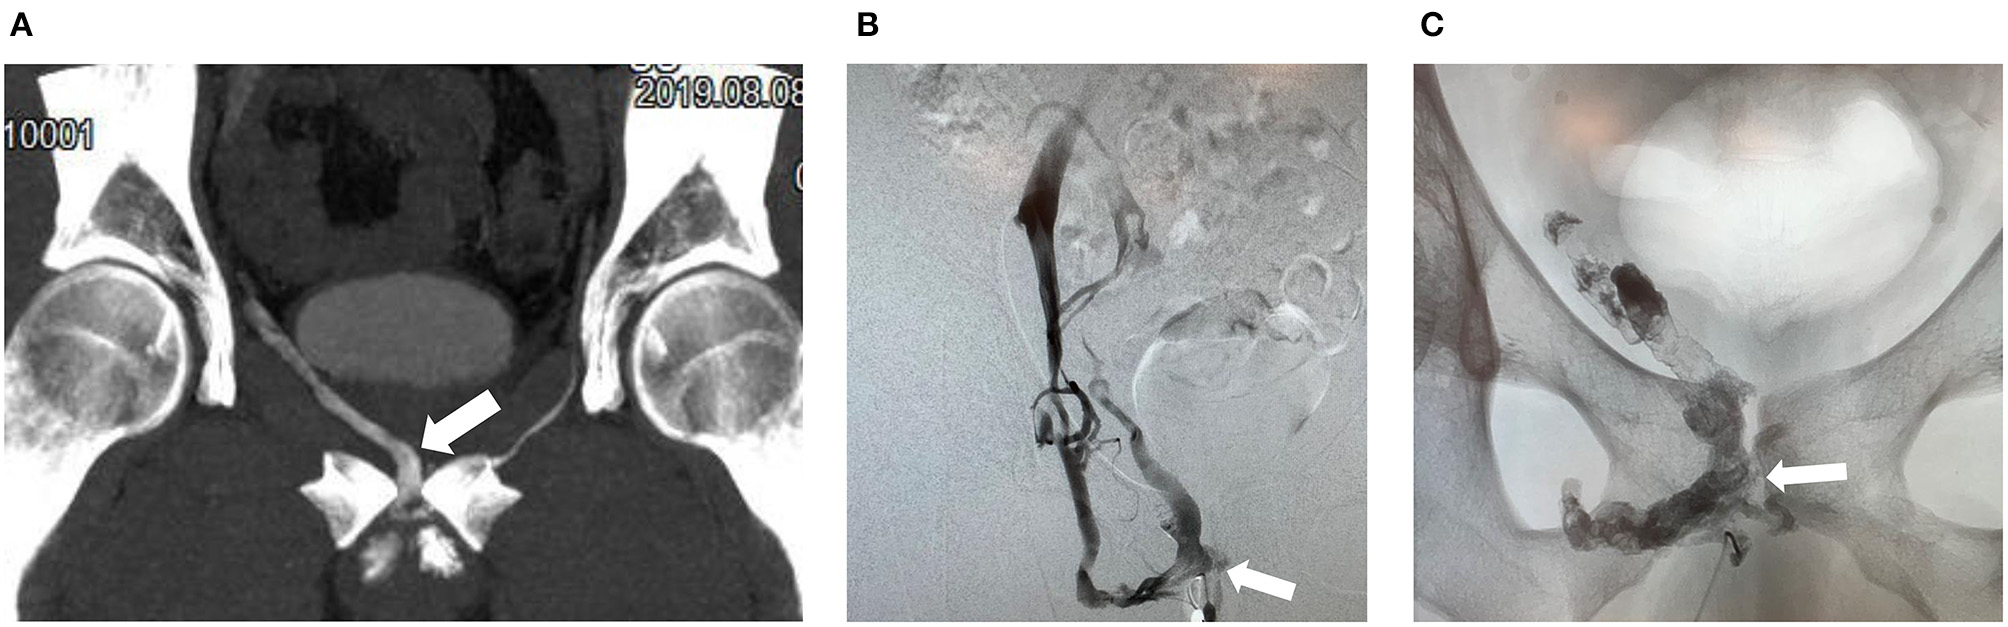

Figure 2

50-year old man with erectile dysfunction due to veno-occlusive disease. (A) Contrast enhanced CT cavernosography (coronal maximum intensity projection) demonstrates right sided venous leak via periprostatic veins (arrow). (B) Cavernosography with access via the deep dorsal vein and injection of contrast medium demonstrates right sided venous leaks predominatentely via periprostatic veins (arrow). (C) Post embolization of periprostatic veins (arrow) using N-butyl-2-cyanoacrylate mixed with Lipiodol demonstrating radiopaque intravenous embolization material (arrow).